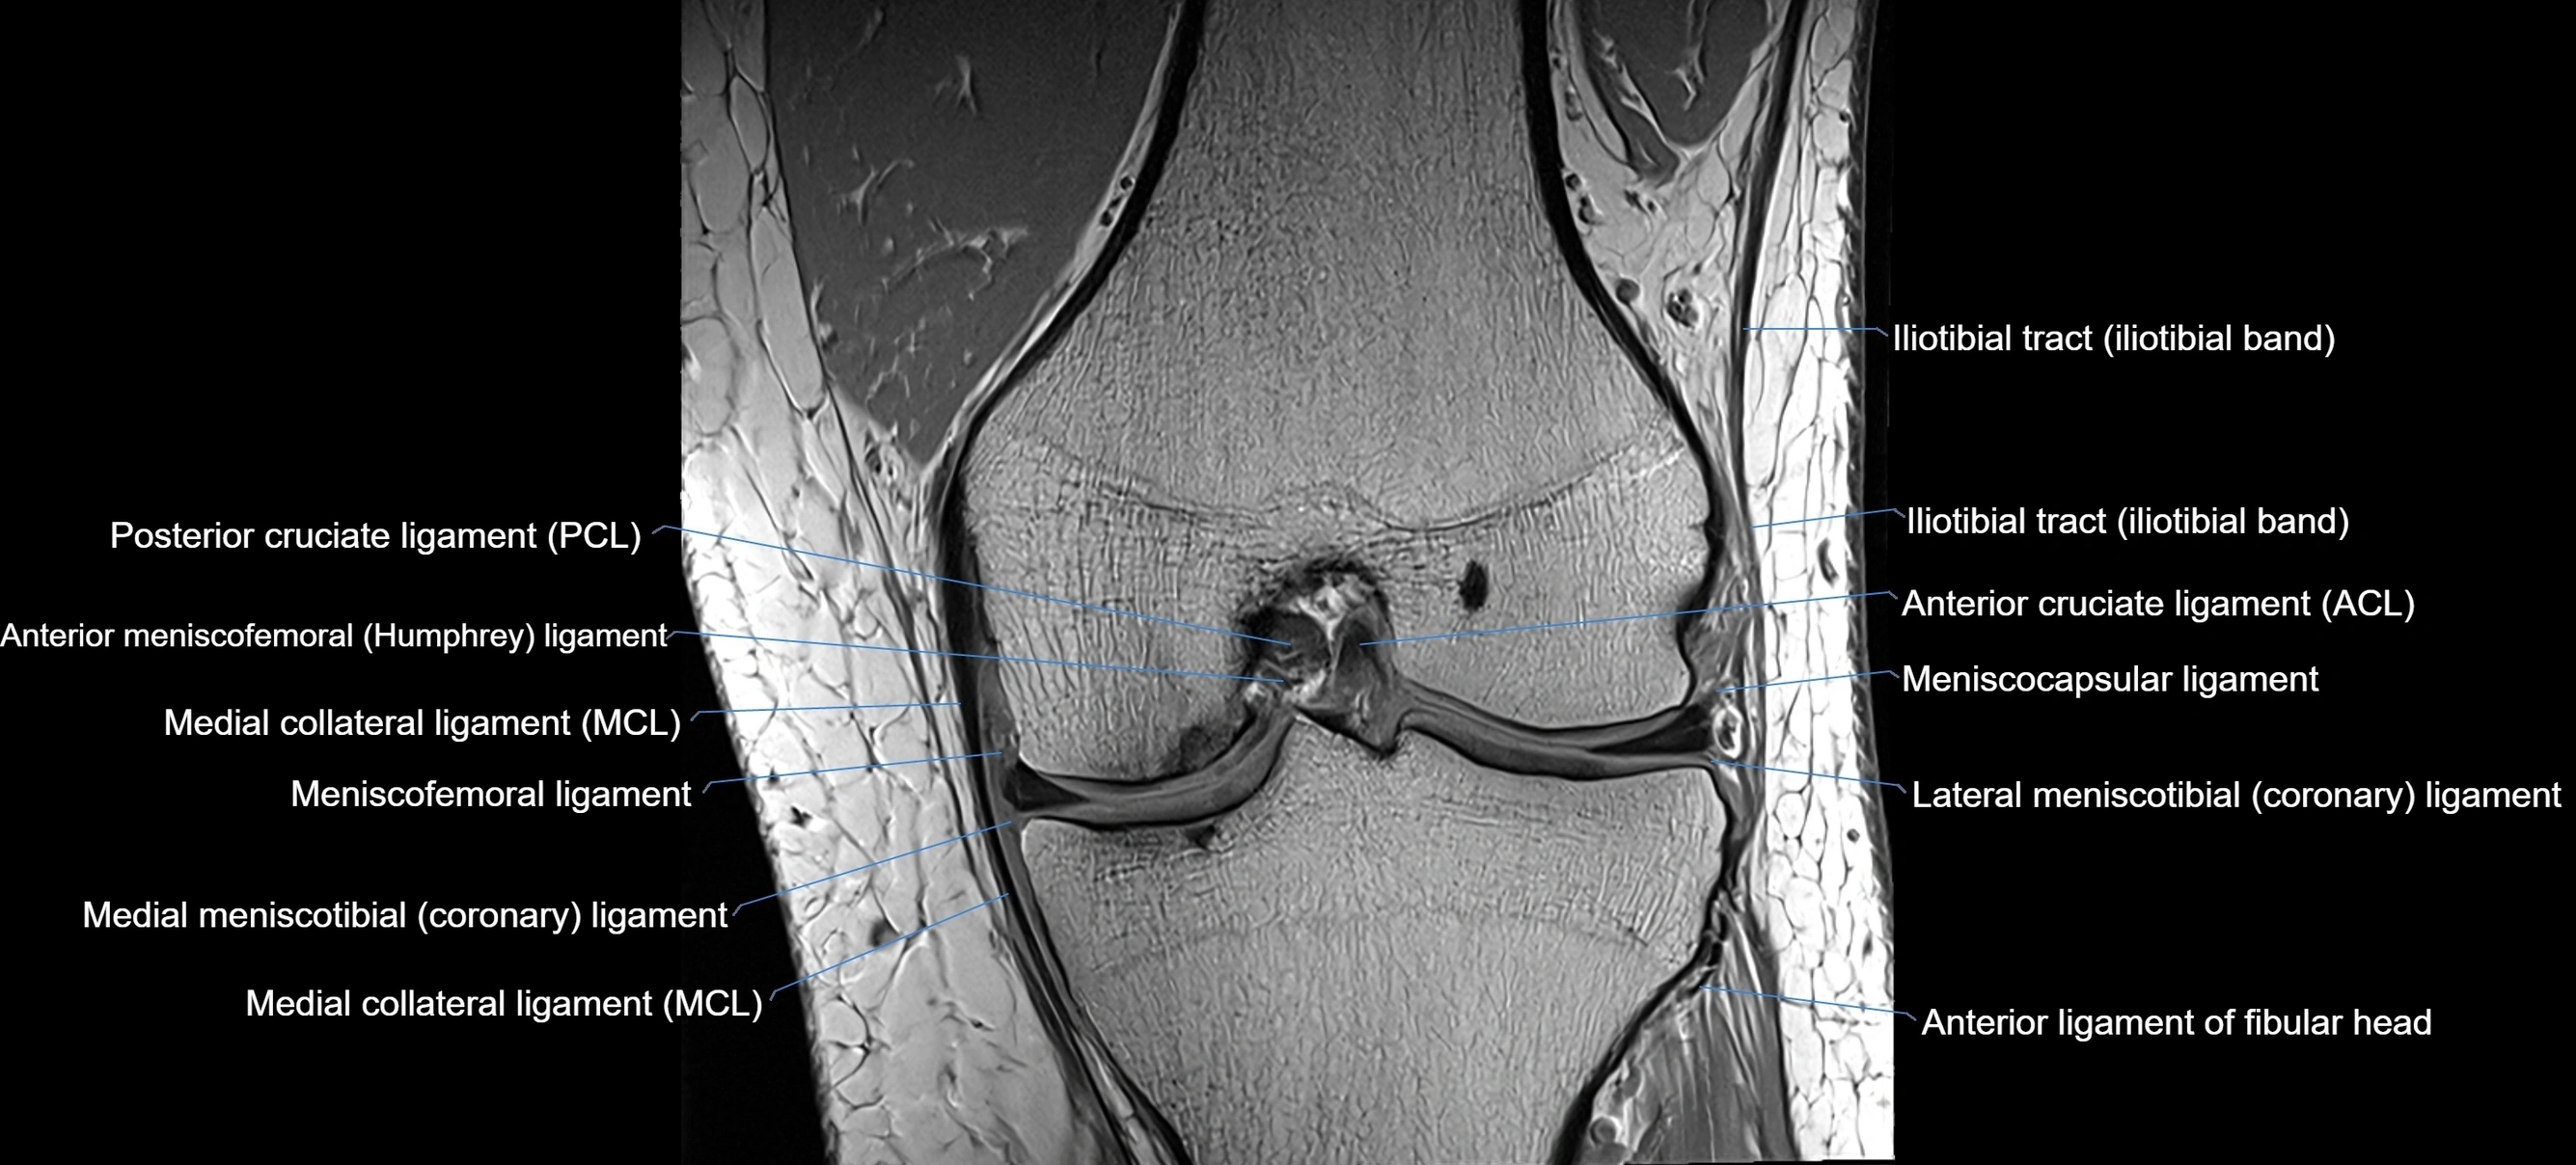

MRI images

image

MRI Appearance

T1-weighted images:

• Normal ACL appears as a low-signal band-like structure crossing the intercondylar notch

• Surrounded by intermediate signal synovial fluid and fat planes

T2-weighted images:

• Normal ACL remains low signal

• Partial or complete tears appear as discontinuity, increased signal, or fiber laxity